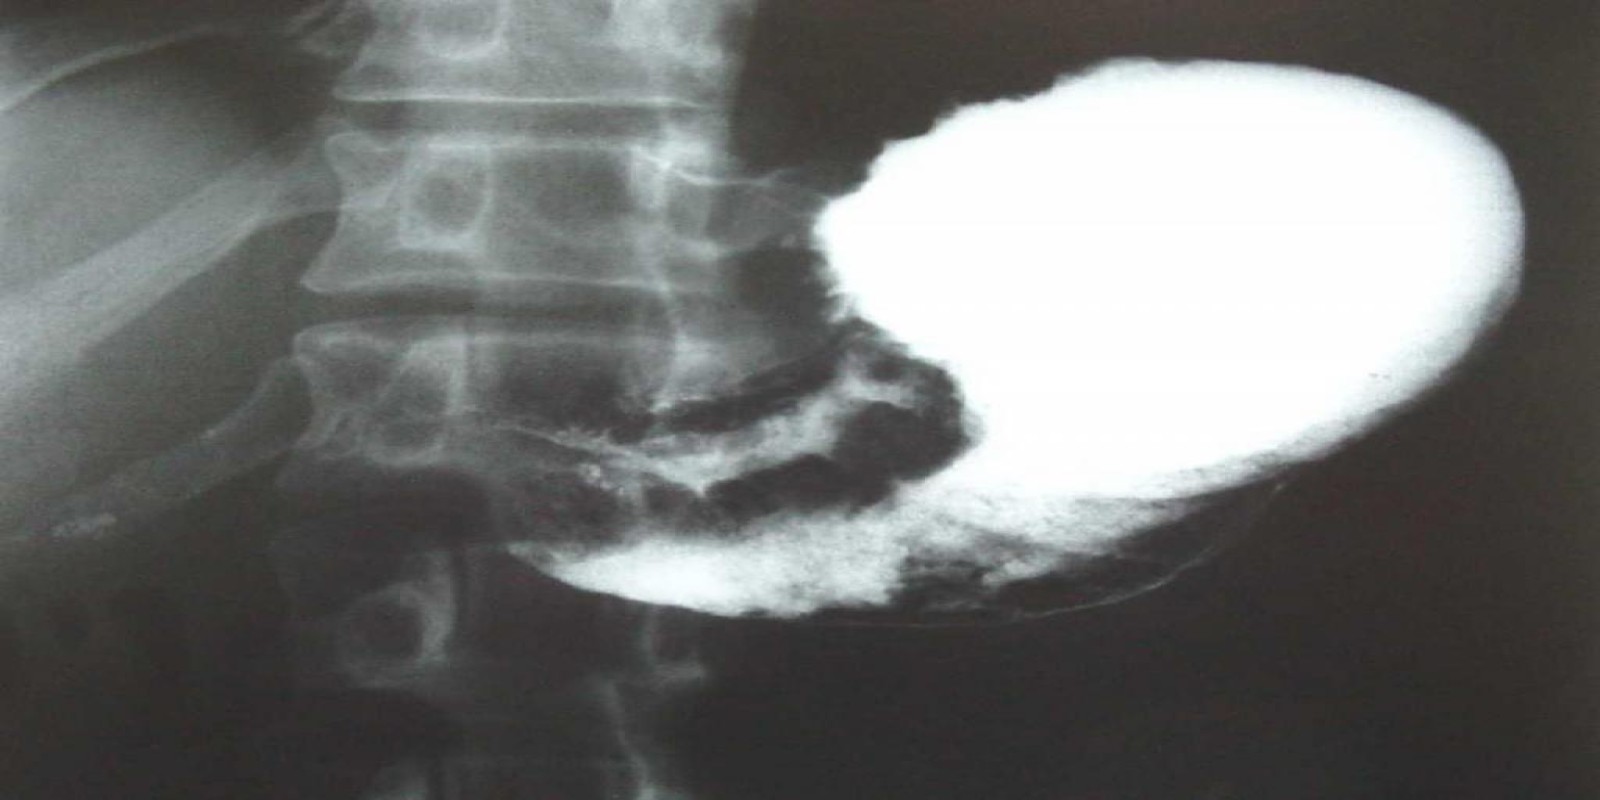

Caso Código 040D de Câncer Gástrico

Cod.: 040D